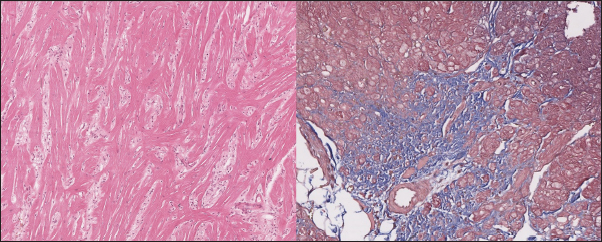

In the myocardial samples of healthy cats, we did not find any significant structural alterations. The cardiomyocytes were presented as cell stripes with one or two centrally located nuclei, Z disks were easily recognized, and striation was presented. The interstitial spaces were not expanded, and the capillary lumen was noticed. Masson’s trichrome staining for fibrosis did not reveal a significant increase in collagen fibers, with sporadic fibers observed in interstitial spaces and near vessels (Fig. 3). Immunohistochemical staining for Cx43 revealed the typical distribution of proteins accumulated in cell-to-cell connections via intercalated disks. Weak-to-absent signals were observed in the lateral wall of the cardiomyocytes. The immunoadsorption zone exhibited a solid line without disruptions or lesions (Fig. 4).

Fig. 3. Histomorphology. Left—Normal myocardium of the cat. Stained with H&E. Right—Normal myocardium of the cat. Red- myocardium; blue—collagen fibers. Stained with Masson’s trichrome.

In the myocardium of cats with HCM we found a typical myocardial fibers disarray, with myocytes presented as thickened stripes branching in chaotic ways. Moreover, significant interstitial fibrosis was observed. Some myocytes were hypertrophied with multiple eccentrically located nuclei. Masson’s trichrome-stained samples showed myocardial fibrosis with interstitial and patchy patterns distributed around arteriolas and deep in the tissues (Fig. 5). Immunohistochemical staining with anti-Cx43 antibodies showed almost intact intercalated disks morphology in unaffected zones, but Cx43 expression began to fade near areas of developed fibrosis. In the transverse axis, we found increased expression of Cx43 on the lateral membrane (Fig. 6). In cardiomyocytes directly connected to the fibrotic tissue, cell-to-cell contacts were pale with almost no staining (Fig. 7).

Fig. 5. Histomorphology. HCM group. Left—Myocardial fibers disarray, atypical branching, interstitial fibrosis. Stained with H&E. Right—Interstitial and patchy fibrosis, cardiomyocytes vacuolar dystrophy. Redmyocardium; bluecollagen fibers. Stained with Masson’s trichrome.